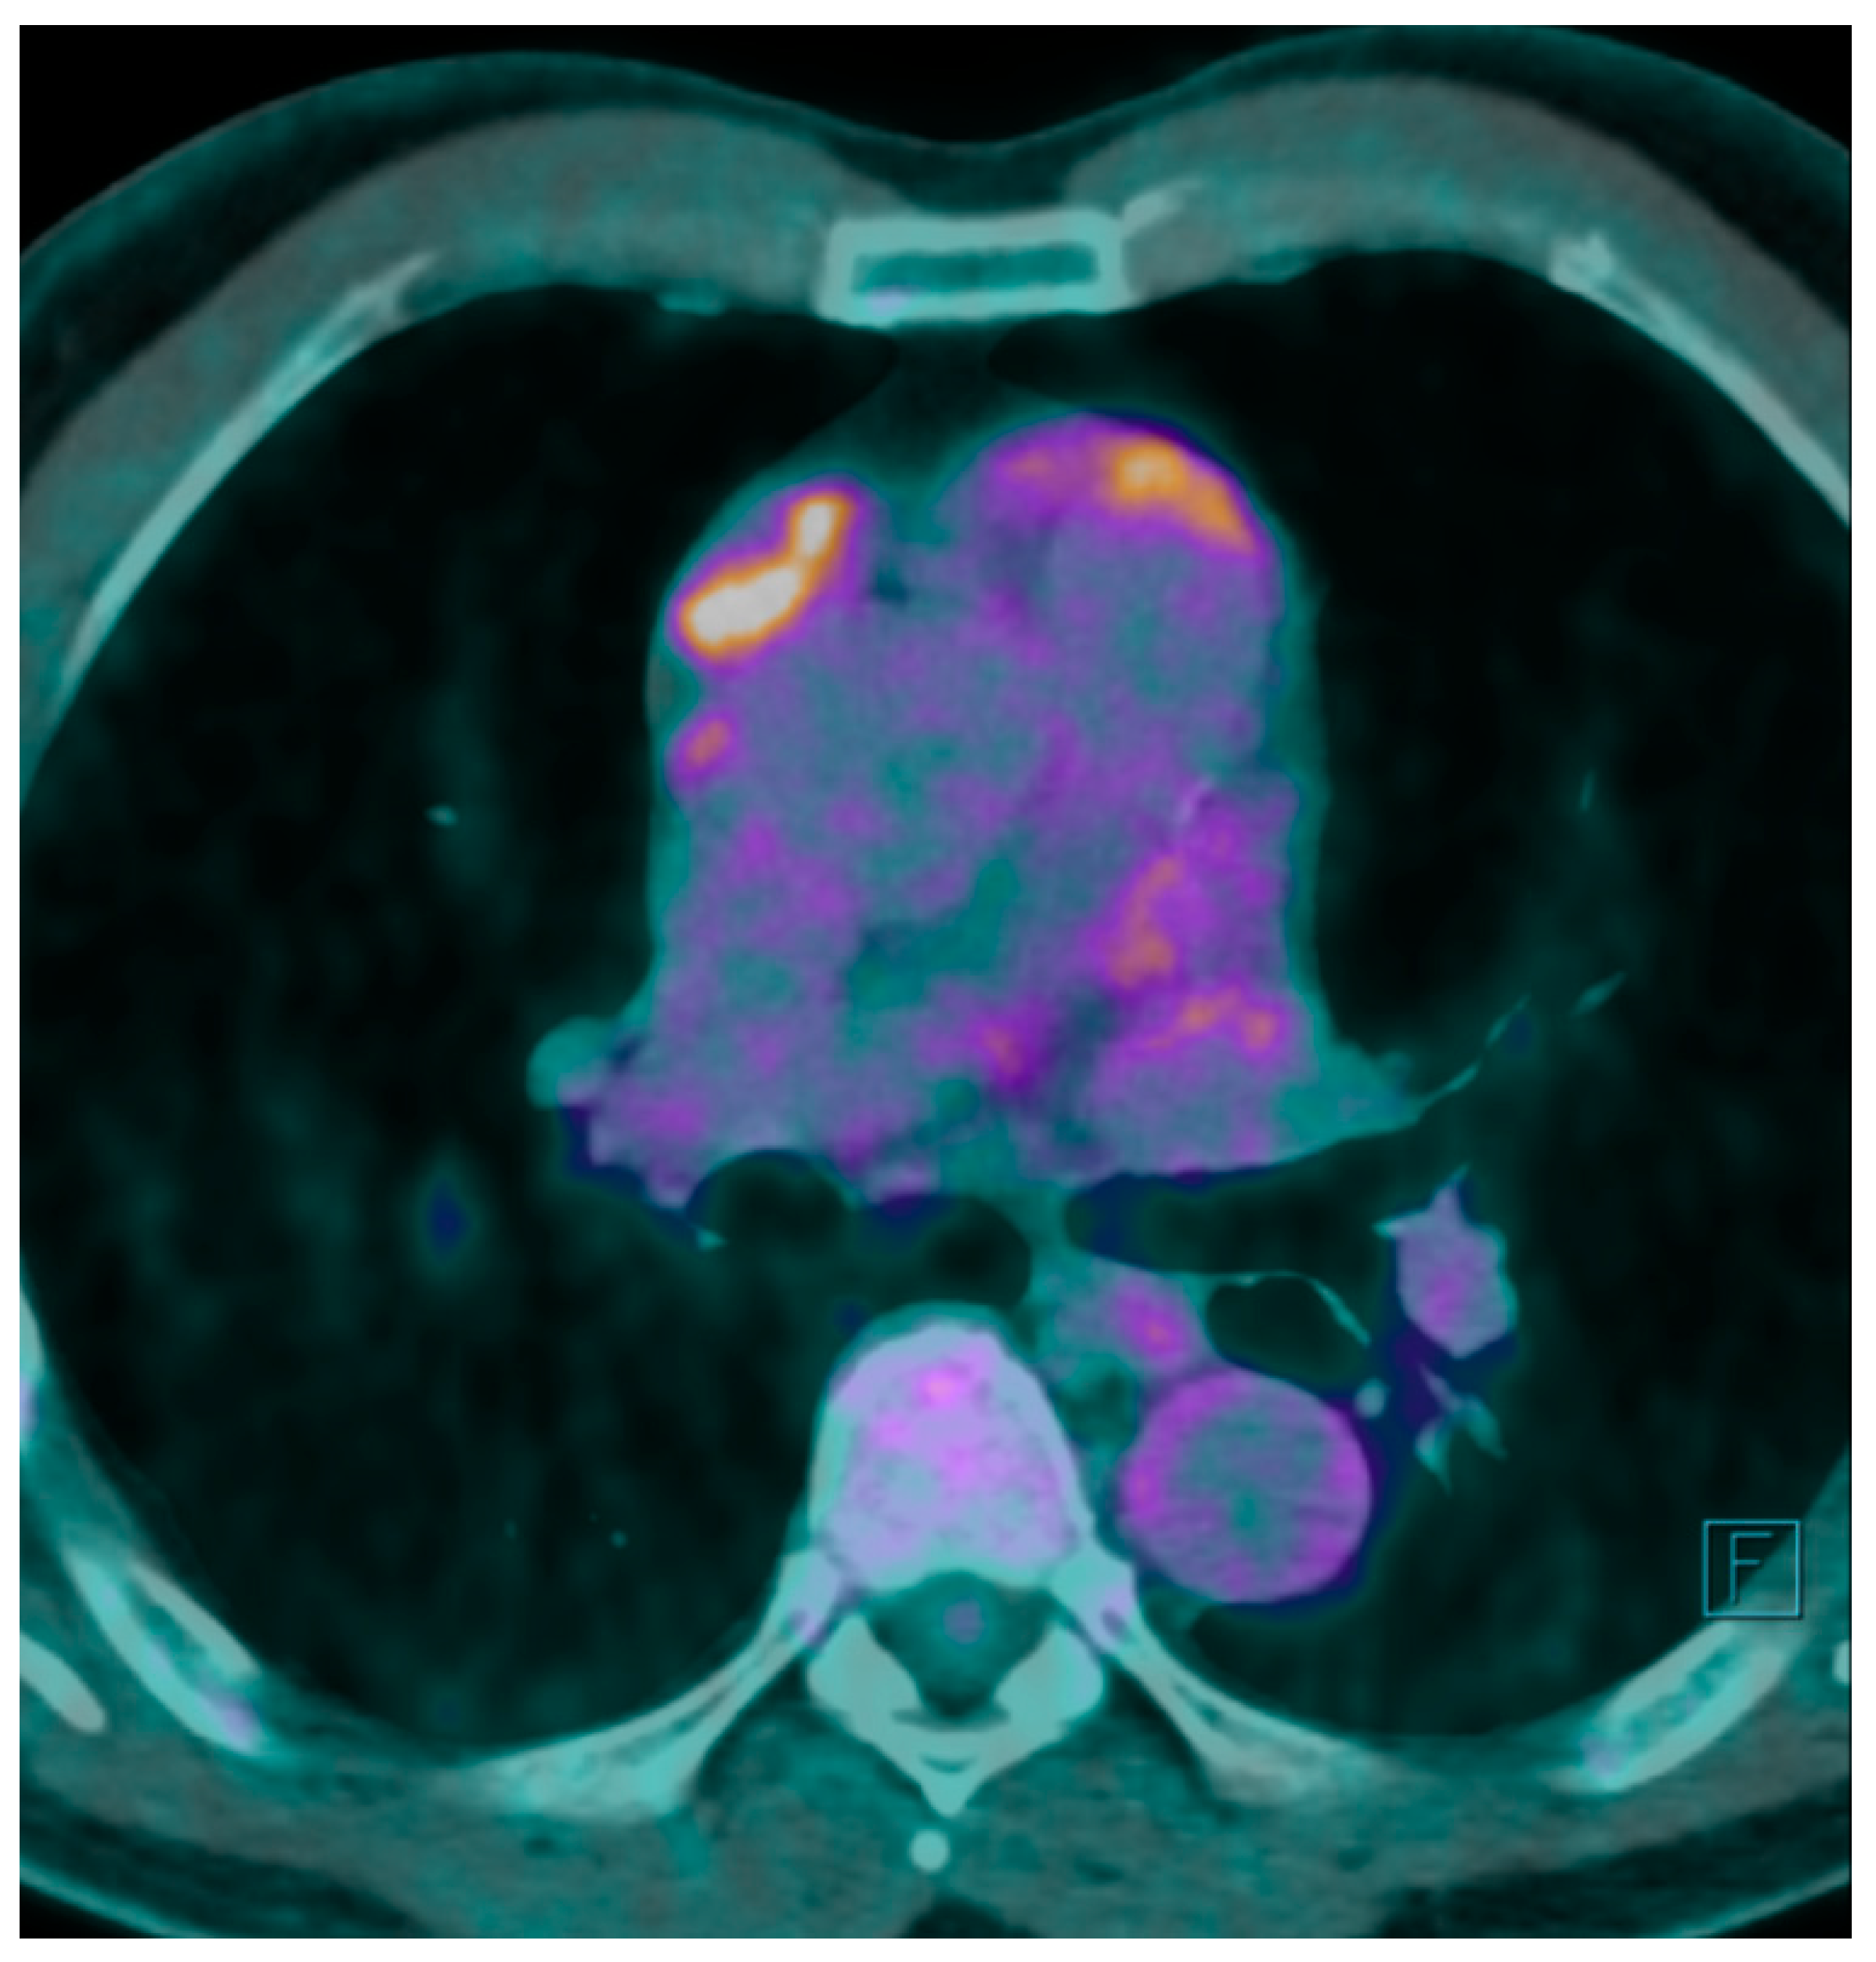

A F

18 fluorodeoxyglucose-positron emission tomography (F

18 FDG-PET) scan was performed showing a maximum F

18 FDG Standard Uptake Value (SUV) of 7.7 at the level of the mass. The FDG uptake appeared to be heterogeneous for the presence of photopenic areas mainly due to the cystic aspect of the mass (

Figure 1).